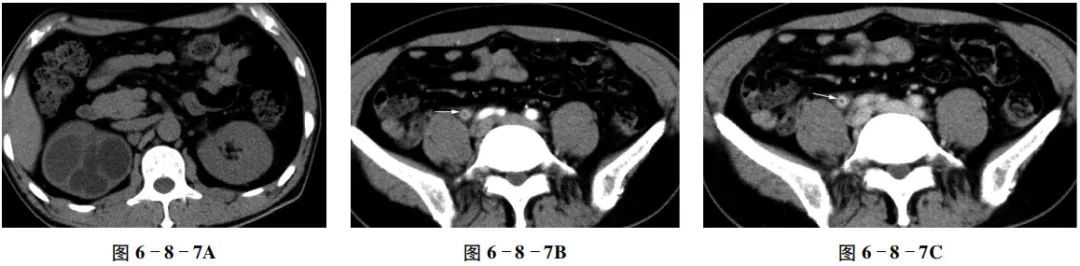

先来看一个案例:男性,45岁,因右肾积水就诊。患者CT表现如下↓

平扫示右侧肾盂、肾盏扩张,右肾实质明显变薄(图6-8-7A);增强扫描示右侧输尿管管壁增厚、毛糙,明显强化,并且输尿管中下段狭窄,周围可见渗出影,(图6-8-7B~D)。

【CT拟诊】

①慢性输尿管炎、肾盂积水。

②多发肾囊肿。

③肾盂旁囊肿。

④多囊肾。

【最终病理诊断】

输尿管纤维增生及慢性炎症性狭窄,右肾积水。